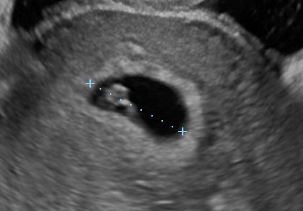

胎嚢の中に、丸い輪のように見える卵黄嚢が見え始めます。卵黄嚢は、赤ちゃんに栄養を送っています。6週の終わり頃には、胎芽と呼ばれる赤ちゃんの姿が確認できることもあります。胎芽がチカチカと輝いているのが、赤ちゃんの心拍となります。